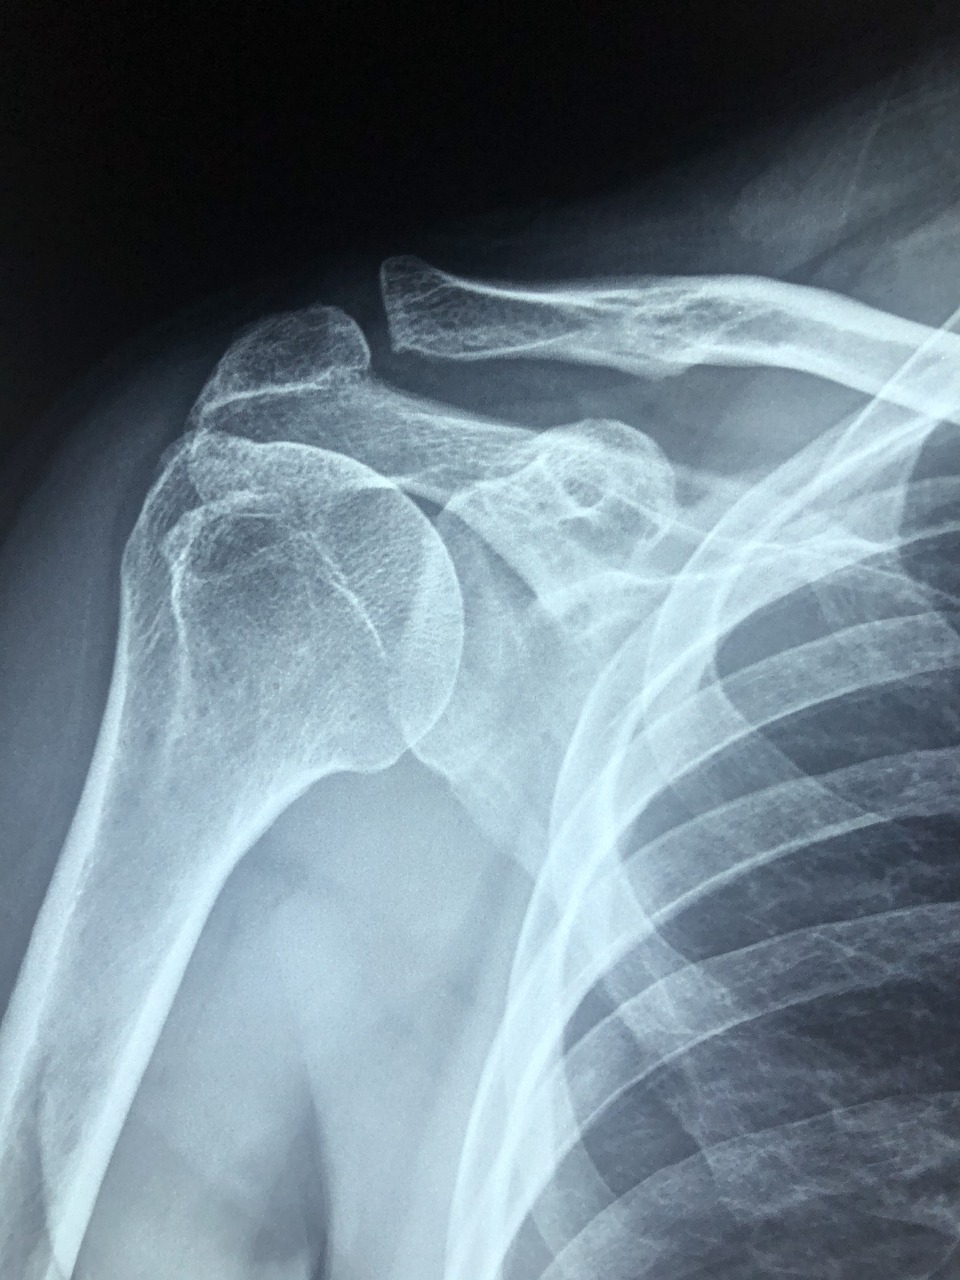

50대 이후 어깨 회전근개 파열